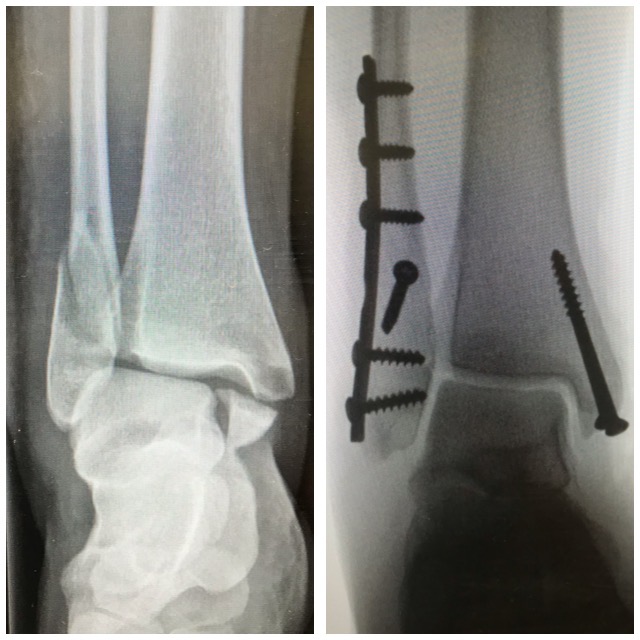

Nilkkamurtuma

Murtumakuvia

Ennen – jälkeen